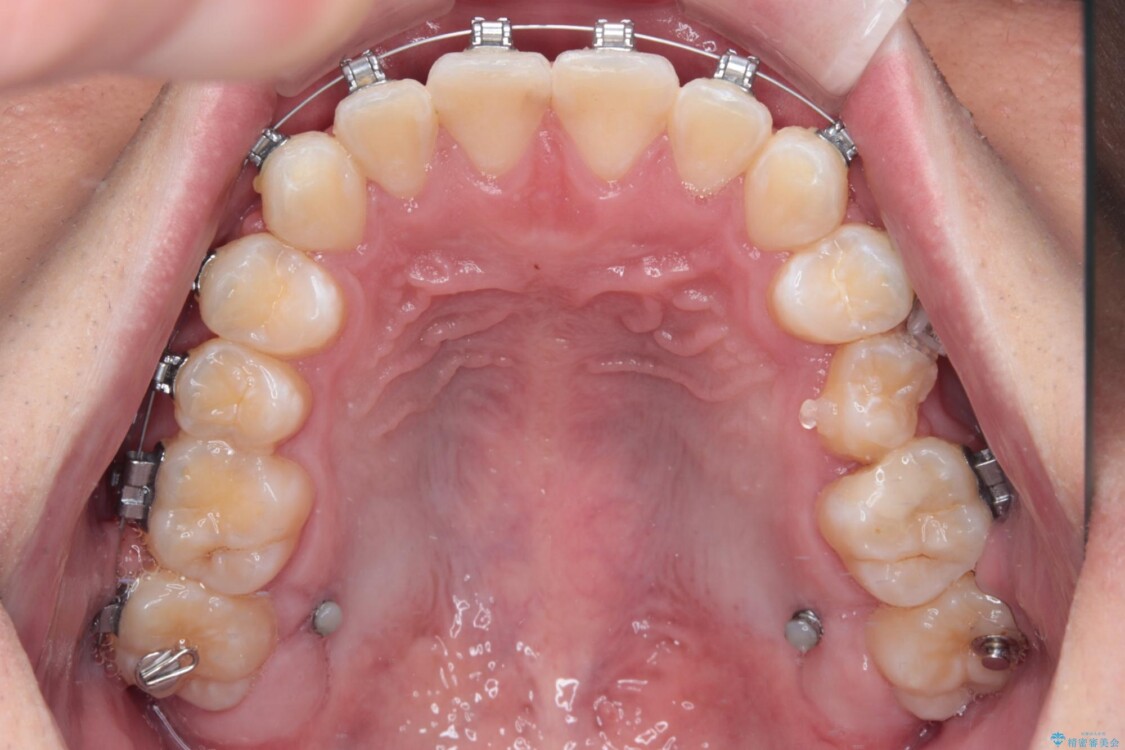

・上顎左右の第二大臼歯が頬側へ転移し、シザーズバイト(scissors bite)の状態

・上顎左側第二小臼歯が90度捻転しており、噛み合わせに影響

・奥歯のシザーズバイト改善には、口蓋側にアンカースクリュー(TAD)を設置し、矯正用ゴムで内側に牽引

・捻転した第二小臼歯は、ワイヤーと矯正用ゴムの力を用いて正しい位置へ回転移動

治療途中

• 前歯のガタガタ・奥歯のかみ合わせ(シザーズバイト)を改善|1年半で完了したメタルブラケット矯正 治療途中画像